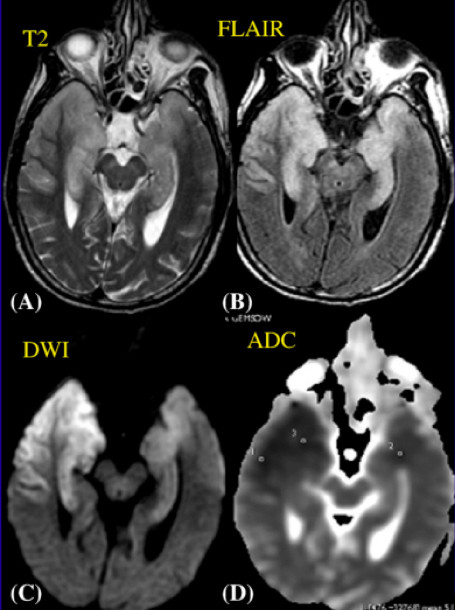

弥漫性脑部缺血 - 缺氧改变

DWI 和 ADC 图是显示早期缺血 - 缺氧脑组织信号改变最好的序列(优于 T2WI 和 FLAIR),早期即有明显的 DWI 高信号及 ADC 低信号改变,最常发生在分水岭区域的皮质 / 皮质下,基底节区也常累及。有明确脑部弥漫性缺血缺氧病史,如心跳骤停,该疾病不难诊断。图 5 为典型影像表现。

图 5 心跳骤停患者,弥漫性脑部缺血 - 缺氧改变,A~D 为 DWI,E~H 为 FLAIR,可见弥漫的双侧皮层高信号